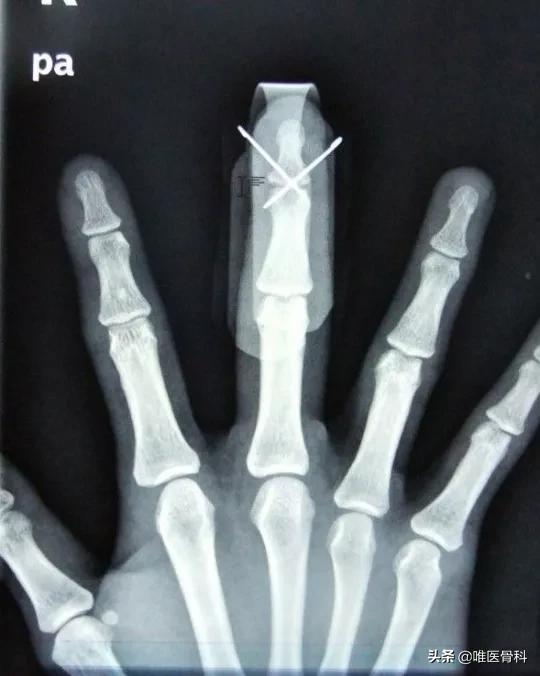

对于靠近关节部位的钢板,由于我们对于关节的功能要求很高,存留的异物有时会成为影响关节活动的罪魁祸首。如肩锁关节部位的锁骨钩钢板,脚踝部位的螺钉、手指或者掌骨的克氏针等,如果不取出来都会影响关节活动。在一些身体的特殊部位,比如皮肤菲薄的小腿,爱美女性的锁骨,钢板很容易触及,一方面摸着不舒服,另一方面钢板与皮肤反复摩擦容易损伤娇嫩的皮肤,甚至还可能造成皮肤破损。这些情况下,可能取出钢板对自己更为有利。